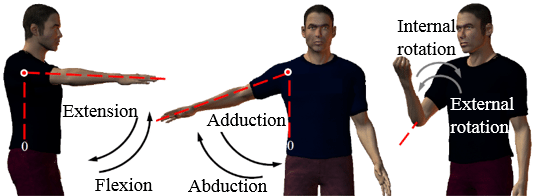

| [Anatomy] Shoulder(어깨) (0) | 2024.01.24 |